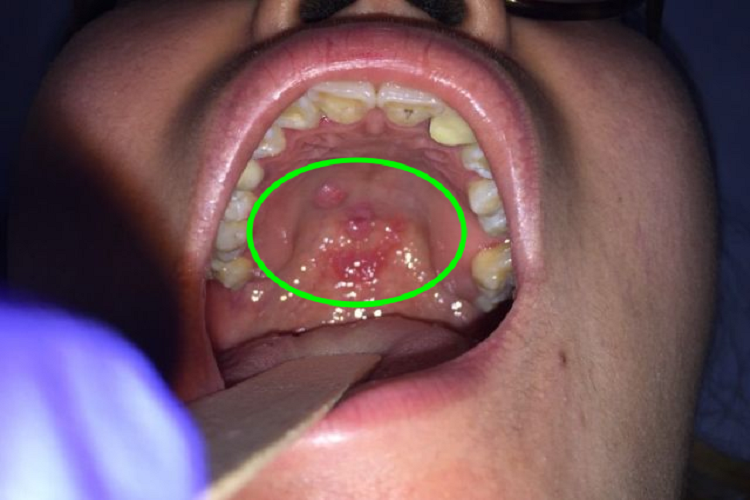

口腔梅毒累及咽峡部位时,局部可出现大小不一、数量不等的红点,邻近皮损之间可互相连接、融合成不规则片状红斑,与周围黏膜的边界清楚,自觉有疼痛不适。